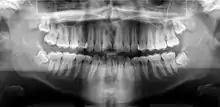

Panoramic radiograph

A dental panoramic radiograph, showing the maxilla and mandible, all the teeth including the "wisdom teeth," the frontal and maxillary sinuses, the nasal cavity and the temporomandibular joint and other near by head and neck anatomy.